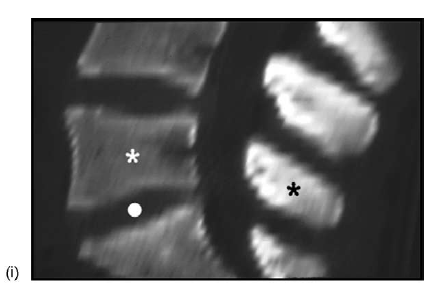

(i) midline sagittal T1-weighted MRI showing hyperintensity of the interspinous ligaments at multiple levels (asterisks). (ii) Midline sagittal T2-weighted, fat-suppressed MRI showing isolated hyperintensity of the L5-S1 interspinous space (arrow) indicating degeneration and possible cystic alteration of the interspinous ligament (compare with (A)). (iii) Coronal T1-weighted MRI showing the rounded appearance of the interspinous ligament (arrow), between the spinous processes of L5-S1 (dots).

(iv) Coronal T2-weighted, fat-suppressed MRI showing again the apparent cystic degeneration of the interspinous ligament situated between the spinous processes of L4 and L5 (dots; compare with iv). (v) Axial T1-weighted MRI showing multiple rounded paraspinous soft tissue structures (arrows); also note the spinous process of L5 (black dot) and the redundant-hypertrophic inter-supraspinous ligament(s) (white dot) (compare with (D)). (vi) Axial T2-weighted, fat-suppressed MRI showing the hyperintense nature of the paraspinous cysts (arrows; same patient in (E) v–vi).